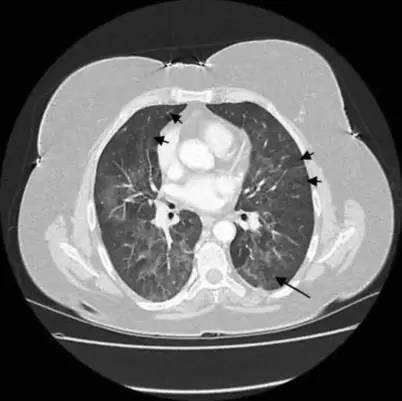

急性期胸部CT表现为两肺弥漫的磨玻璃密度影或广泛的实变影,主要分布在中下肺(如图7)。

图 7:OHP急性期胸部CT表现